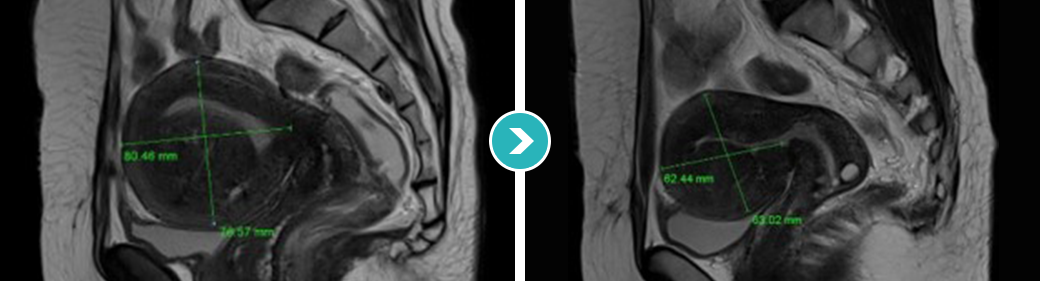

3STEP HIFU PROGRAM 2010년 부터 오직 자궁근종과 자궁선근증의 안전한 치료를 위해 전 과정MRI통합 하이푸 치료 프로그램 운영

시술 전 악성화 병변으로의 변화의 가능성 확인 및 숨어있는

악성 병변을 분석하는 MRI 촬영

시술과정 초음파영상과 MRI영상 콜라보 모니터링

시술 후 하이푸 치료 브리핑 및 객관적 평가

MRI촬영으로 자궁근종의 상태(위치, 개수, 크기, 모양 등), 자궁근종의 혈액공급 및 혈류,

자궁근종과 인접한 주요장기 및 구조, 초음파 발사경로의 확보 등을 분석함. 또한, 정밀초음파는 제거할 자궁근종의 개수, 자궁근종의 치료 슬라이스 수와

각 슬라이스의 체적, 근종제거마진, 근종과 인접한 장기와의 상관관계 등을 분석합니다.

전사적으로 시행함으로써 하이푸 시술의 안전도와 치료효과를 높이는 통합 MRI하이푸 프로그램입니다.

시술 전 MRI검사 결과를 바탕으로 자궁근종이나

자궁선근증 등 종양의 위치, 크기, 모양 등 정확하게 파악